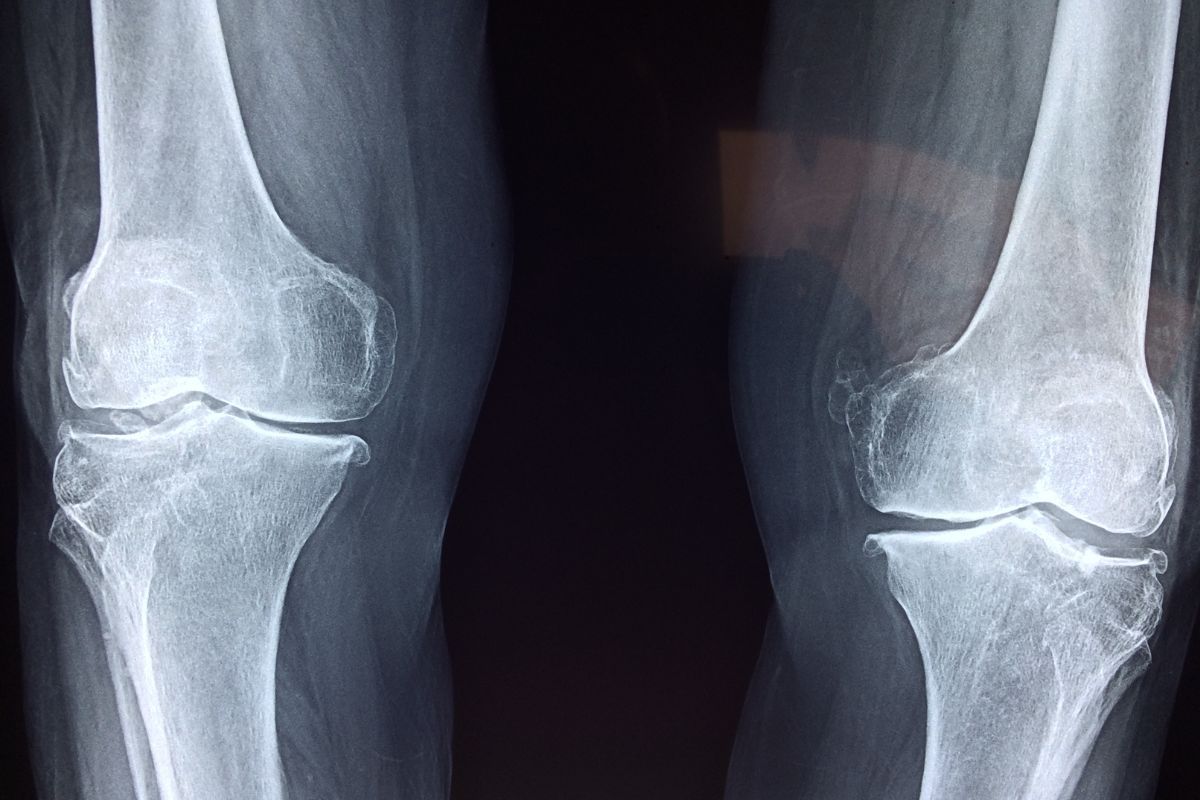

स्रोत विज्ञान एवं टेक्नॉलॉजी फीचर्स | भारत में बड़ी संख्या में लोग अधेड़ उम्र से ही घुटने के दर्द जैसी समस्याओं से जूझते हैं। कुछ मामलों में तो लोग ठीक से चल भी नहीं पाते या चलते-चलते अक्सर गिर जाते हैं। दरअसल यह अस्थिछिद्रता (ऑस्टियोपोरोसिस) नामक स्थिति है जिसमें हड्डियों का घनत्व कम हो जाता है और वे भुरभरी हो जाती हैं। हल्की-सी टक्कर से उनके टूटने की संभावना बढ़ जाती है। एक बड़ी समस्या यह है कि इस स्थिति पर तब तक किसी का ध्यान नहीं जाता जब तक कोई गंभीर चोट न लग जाए। यह दुनिया भर में 50 से ज़्यादा उम्र की लगभग एक तिहाई महिलाओं और 20 प्रतिशत पुरुषों को प्रभावित करती है। संभव है कि भारत के तकरीबन 6 करोड़ लोग अस्थिछिद्रता से पीड़ित हैं, लेकिन इसके सटीक आंकड़े जुटाना काफी मुश्किल है।

प्रदूषण व अस्थिछिद्रता के बीच इस सम्बंध से प्रदूषण कम करने के लिए प्रभावी कार्रवाई की आवश्यकता स्पष्ट है। इसके अतिरिक्त, अस्थिछिद्रता के निदान को बेहतर करना ज़रूरी है। अस्थि घनत्व की जांच के लिए ज़रूरी DEXA स्कैनरों की भारी कमी है, जो महंगे हैं और मात्र बड़े शहरों में उपलब्ध हैं। समय पर समस्या का पता चलने से हड्डियों के स्वास्थ्य को बेहतर बनाने में मदद मिल सकती है। फिलहाल अस्थिछिद्रता से पीड़ित बहुत से लोग बिना निदान और इलाज के तकलीफ झेलते हैं, जो वायु प्रदूषण जैसे पर्यावरणीय कारकों से और भी बढ़ जाती है। (स्रोत फीचर्स)